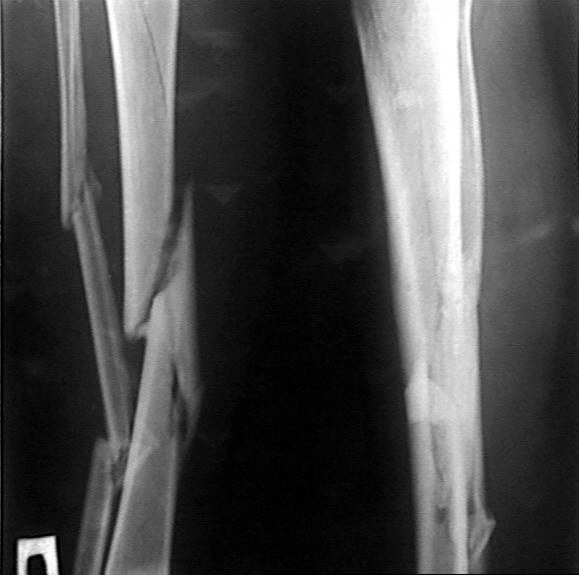

Диагноз: двойной оскольчатый перелом правого бедра в с/3 и н/3 со смещением, открытый оскольчатый перелом правой большеберцовой кости в с/3 со смещением двойной перелом малоберцовой кости. Оперирован проведена открытая репозиция, остеосинтез двумя пластинами бедренной кости, иммобилизация кокситной повязкой. На контрольных рентгенограммах от 21 01 04 имеется: несостоятельность остеосинтеза бедренной кости в в/3 выраженная угловая деформация; консолидирующийся перелом большеберцовой кости со смещением по длинне и выраженной вальгусной деформацией. Родственникам рекомендовали оперативное лечение. Больного доставят на осмотр 28.01.04, обдумываем способы лечения. Оперативное лечение планируем в два этапа, вначале на бедре, затем на голени. На бедре- удаляем верхнюю пластину, проводим остеотомию по линии верхнего перелома, проводим репозицию, остеосинтез пластиной с фиксацией верхнего, среднего и нижнего фрагментов.На голени-мнения разделились:- можно наложить аппарат внешней фиксации на голень, провести остеотомию б/берцовой кости в зоне перелома между проксимальным отломком и осколком, остеотомию малоберцовой кости, провести постепенную репозицию, тибиализацию (рисунок 3).-или провести остеотомию по линии перелома большеберцовой кости, репонировать и фиксировать пластиной. Новосибирская областьг Куйбышев ЦРБСергей Зырянов

Привет Сергей! Разделять вмешательства на этапы рационально, если соматический статус больного нестабильный или Ваши анестезиологи не смогут по той или иной причине обеспечить вмешательство в один этап. Я бы предложил вмешательство в один этап: на бедре ресинтез "нормальной пластиной" на 18-20 винтах с дистальным клинком, выбросив "негодный металлолом"- все равно придется металл убирать, даже если планировать внутрикостный синтез стержнем с блокированием, на голени аппарат по классической схеме без перемещения фрагмента м\б кости. Периоперационное обеспечение крайне важно: спинально-эпидуральная анестезия с пролонгированием обезболивания, кровосбережение, профилактика ТЭЛА и инфекции классические. Судя по

рентгенограммам -проблем с остеорепарацией у больного нет - проблемы с некачественным остеосинтезом привели к данной ситуации. Желаю успеха и удачи.